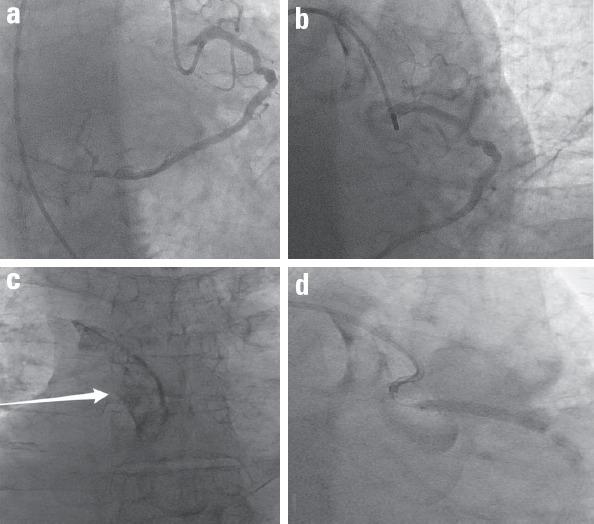

Successful management of iatrogenic retrograde dissection into the aortic root.

Anatol J Cardiol. 2017 Sep;18(3):235-237. doi: 10.14744/AnatolJCardiol.2017.7803.